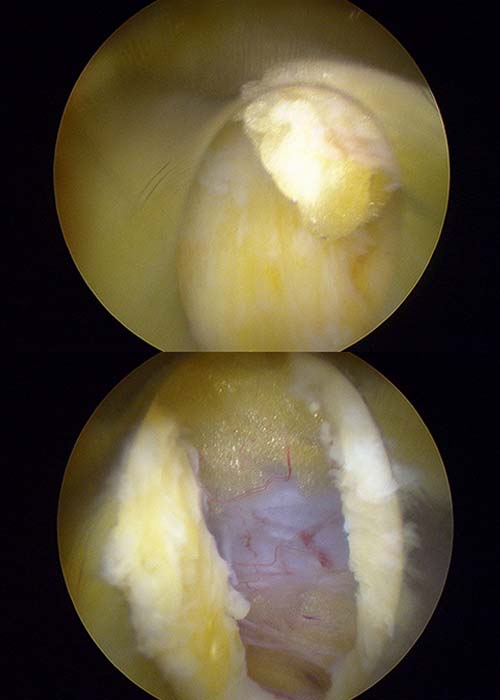

Operamos al paciente mediante una técnica de endoscopia mínimamente invasiva sin producir ningún daño en sus tejidos.

Para este tipo de operaciones, introducimos una aguja que sirve como guía y, dentro de ella, un dilatador que nos permite no perjudicar ni dañar ningún tejido neurológico, muscular u óseo. Posteriormente, accedimos a la zona que queríamos trabajar a través de la cánula. Con un vaporizador especial formado por una punta de láser que trabaja con radiofrecuencia, vamos cauterizando o retrayendo los tejidos. Dicho aparato quirúrgico, nos ayuda identificar de manera óptima y precisa las estructuras que debemos ir limpiando.

Gracias a esta operación, conseguimos eliminar por completo la compresión del nervio, logrando de manera óptima la circulación de la sangre alrededor de la zona mencionada y descomprimiendo de manera completa todas las estructuras neurológicas.

paciente-con-hermia-discal